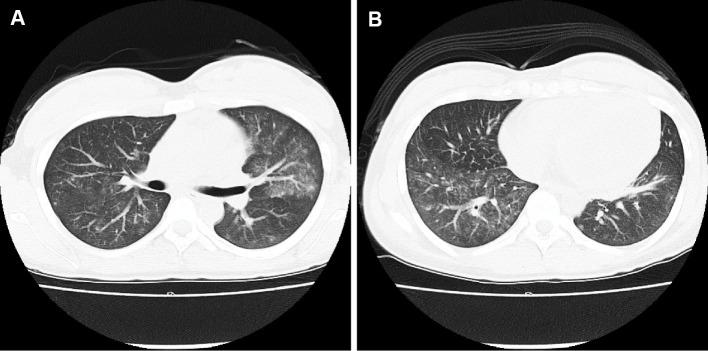

A 21-year-old woman was admitted to our hospital because of massive intestinal bleeding. She started hemodialysis due to myeloperoxidase antineutrophil cytoplasmic antibody (ANCA)-associated vasculitis (AAV) at 18 years of age. Her ANCA titers remained stable; however, her C-reactive protein increased on 5 mg/day prednisolone before admission. Computed tomography angiography revealed a ruptured jejunal arterial aneurysm. Transcatheter arterial embolization, blood transfusion and the reinforcement of steroid therapy resolved her symptoms of AAV. Our case of a young patient with AAV and medium-sized arterial vasculitis is rare and emphasizes that the ANCA titer does not always rise, especially in patients with nonrenal vasculitis flare-ups.

一位 21 岁女性因大量肠道出血而入院。她在 18 岁时因髓过氧化物酶抗中性粒细胞胞质抗体(ANCA)相关性血管炎(AAV)开始接受血液透析。她的 ANCA 滴度保持稳定;然而,在入院前,她每天服用 5 毫克泼尼松龙,C 反应蛋白升高。计算机断层血管造影显示空肠动脉破裂性动脉瘤。经导管动脉栓塞、输血和强化激素治疗缓解了她的 AAV 症状。我们的这个年轻 AAV 合并中等大小动脉血管炎的病例比较少见,强调了 ANCA 滴度并不总是升高,尤其是在非肾血管炎发作的患者中。